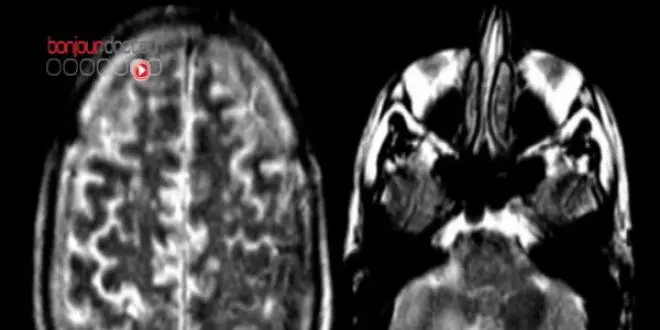

Mais plus incroyable, ils remarquent une chose étonnante chez deux patients : le volume de leur hippocampe a augmenté, de 5 % chez l'un et 8 % chez l'autre.

Il faut savoir que l'hippocampe est une structure cérébrale elle aussi impliquée dans la mémoire. Cet organe agit comme une sorte de péage en faisant passer les données de la mémoire à court terme en mémoire à long terme.

Chez un adulte jeune elle représente un volume d'environ 3 à 4 cm3. Plus on vieillit, plus le volume de l'hippocampe diminue, d'environ 1 % par an pour une personne âgée en bonne santé, de 3 % pour une personne atteinte de la maladie d'Alzheimer. C'est cette perte de volume qui entraîne des pertes de mémoire, voire une amnésie totale.